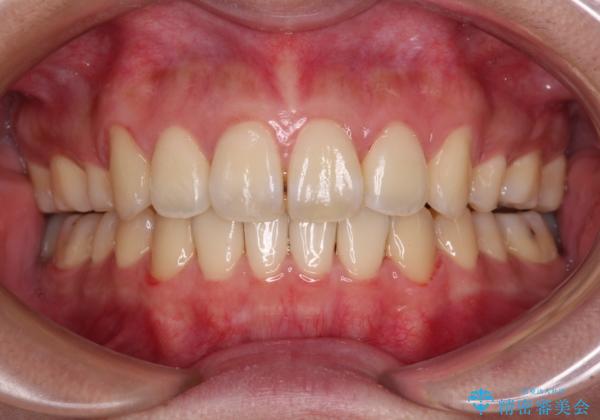

元々奥歯に負担のかかる咬み合わせですり減っていたため、仕上がった歯並びでも奥歯が咬んでいないように見えましたが、実際にはしっかりと咬合しており、患者様本人も咬んだ感触に違和感はないとのことでした。